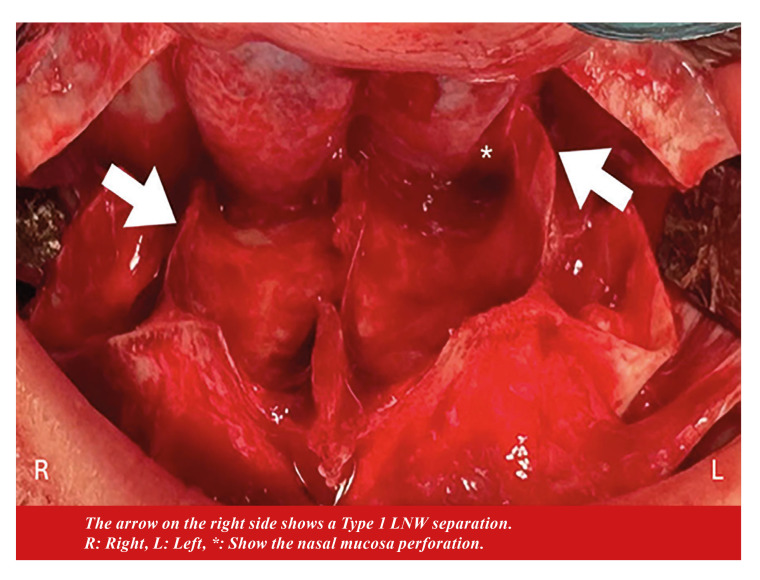

Material and methods: This prospective, controlled, randomized study included forty-three patients were randomly assigned to either the conventional or customized (study) osteotomy groups. In the study group, LNW depth was measured before surgery in the axial section of the CT scan, and LNO was performed at a depth of 2 mm less than the measured distance. In the conventional osteotomy group, LNO was performed at 30 mm for females and 35 mm for males. Patients with cleft lip and palate, previous orthognathic surgery, or rhinoplasty were excluded. Separation types were classified as follows: LNW types; Type1-from the osteotomy line; Type2- 2-4 mm above the osteotomy line; Type3- 4 mm or more above the osteotomy line. PMJ types; Type1-including the tuber maxilla; Type2-from the pterygomaxillary junction; Type3-including the pterygoid plates. Chi-square tests were conducted to determine whether there was a significant correlation between groups and LNW separation types, groups and PMJ separation types and groups, and LNW separation type and PMJ separation type. A P value of < .05 was considered statistically significant.

Results: In both the conventional (P=0.052) and the study groups (p=0.828), there was no significant difference between LNW depth. Type 1 (P=0.0003) and Type 2 (P=0.0051) LNW separation types presented a significant difference between groups. A chi-square test showed a significant correlation between the surgical groups and PMJ separation patterns (P<0.05).